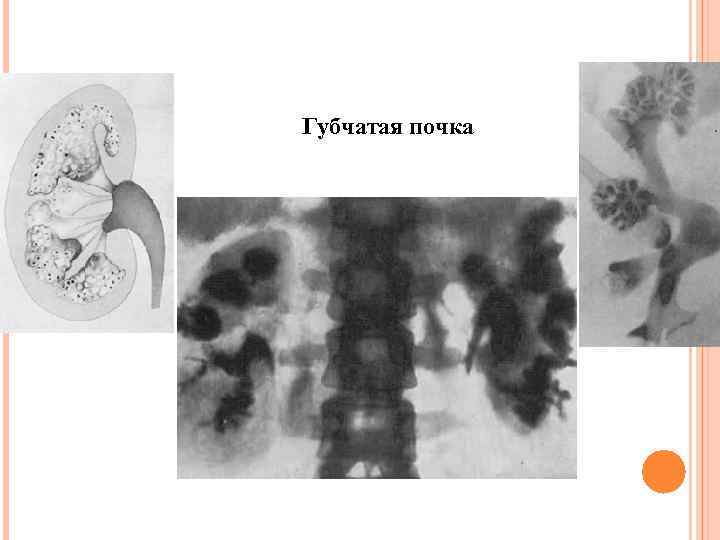

Губчатая почка

Губчатая почка